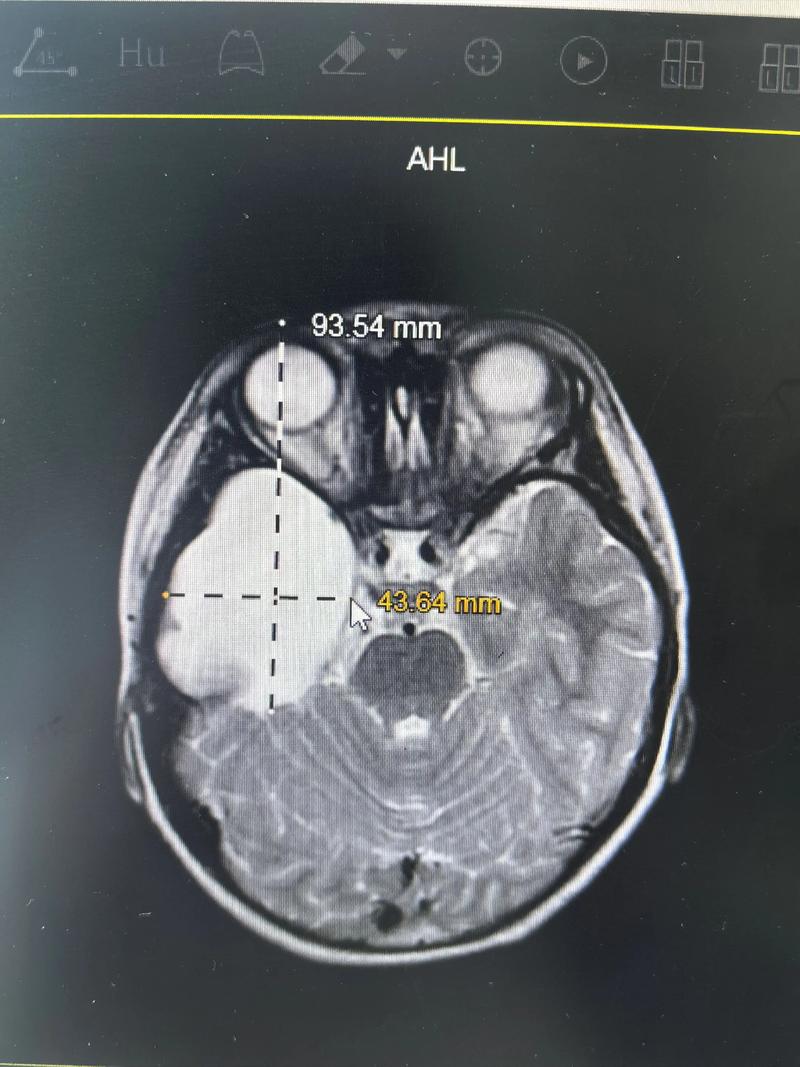

- 磁共振成像:是评估蛛网膜囊肿的“金标准”,它能非常清晰地显示囊肿的大小、位置、形态,以及与周围脑组织、血管和神经的关系,有助于与其他类型的囊肿(如表皮样囊肿)相鉴别。

- 囊肿本身:大小、位置、是否与脑室相通。

- 周围结构:是否对脑组织、脑室系统造成压迫,导致脑积水(脑脊液循环不畅)。